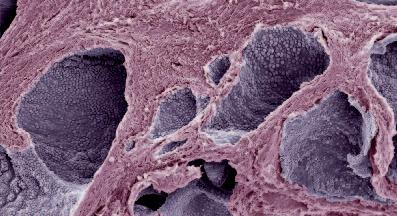

La pagina a fianco mostra l'immagine di una cellula tumorale reale, visualizzata al microscopio elettronico, che ingrandisce questa cellula 6500 volte rispetto alle sue normali dimensioni. Questo tipo di cellula prende il nome di carcinoma, cioè derivante da cellule epiteliali, il tipo di cellule che rivestono sia le superfici interne (polmoni, intestini) che esterne (pelle) del corpo.

Grazie a questo ingrandimento si possono identificare chiaramente alcune delle caratteristiche di tutte le cellule tumorali: a) l'enorme nucleo cellulare dalla forma insolita che spiega la loro grande capacità di riprodursi e b) la struttura non uniforme, complessa della superficie cellulare, che riflette una forte attività di secrezione di sostanze prodotte dalle cellule tumorali.

Una delle più importanti molecole secrete dalle cellule tumorali in grandi quantità sono gli enzimi a ‘forbice’ che digeriscono il collagene. Sono aggiunti graficamente a questa immagine, sotto forma di strutture simili ad un ‘pacman’ rosso.

Nella figura A è possibile vedere la struttura del tessuto di un seno non predisposto per l’allattamento, caratterizzato dalla struttura densa di tessuto connettivo che circonda il condotto del latte, al centro dell'immagine, in gran parte chiuso.

In netto contrasto, la figura B mostra la struttura cellulare di un seno predisposto all’allattamento, caratterizzato da tessuto connettivo lasso, la presenza di cellule della ghiandola principale necessaria per la produzione di latte (piccoli cerchi bianchi), nonché il condotto del latte ampiamente aperto (al centro dell'immagine).

A. Condotto del latte (chiuso) nel tessuto del seno in condizioni normali

B. Condotto del latte (aperto) durante l’allattamento

A Ripresa di un condotto del latte al microscopio, sito in un seno non predisposto all’allattamento (chiuso)

B. In funzione dell’allattamento si ristruttura il tessuto mammario. Il condotto è aperto e il latte può uscire.

La foto nella pagina a fianco mostra una sezione trasversale al microscopio del fegato di un paziente con ‘leucemia linfatica’. Ciascuno dei piccoli puntini viola nella foto è un globulo bianco (in questo caso linfocita) che ha invaso il tessuto del fegato (aree rosa).

Considerando l’enorme quantità di questi puntini viola e il numero di enzimi che assimilano il collagene che ciascuno produce, è facile prevedere l’ingente distruzione del tessuto connettivo e il danno apportato all’organo da questo tipo di cancro.

Immagine al microscopio della leucemia linfatica

Globuli bianchi affetti di cancro (linfociti) invadono il fegato L’enorme quantità di collagenasi prodotte da queste cellule distruggono l’organo e causano insufficienza epatica.